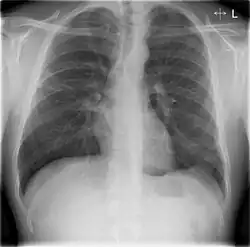

Chest X-rays and X-ray computed tomography (CT) can reveal areas of opacity (seen as white), indicating consolidation.[14] CAP does not always appear on x-rays, sometimes because the disease is in its initial stages or involves a part of the lung not clearly visible on x-ray. In some cases, chest CT can reveal pneumonia not seen on x-rays. However, congestive heart failure or other types of lung damage can mimic CAP on x-ray.[16]

When signs of pneumonia are discovered during evaluation, chest X-rays and examination of the blood and sputum for infectious microorganisms may be done to support a diagnosis of CAP. The diagnostic tools employed will depend on the severity of illness, local practices and concern about complications of the infection. All patients with CAP should have their blood oxygen monitored with pulse oximetry. In some cases, arterial blood gas analysis may be required to determine the amount of oxygen in the blood. A complete blood count (CBC) may reveal extra white blood cells, indicating infection.

Ceftriaxone and azithromycin are often used to treat community-acquired pneumonia, which usually presents with a few days of cough, fever, and shortness of breath. Chest x-ray typically reveals a lobar infiltrate (rather than diffuse).[20]

X-ray findings indicating hospitalization include:

- Involvement of more than one lobe of the lung

- Presence of a cavity

- Pleural effusion